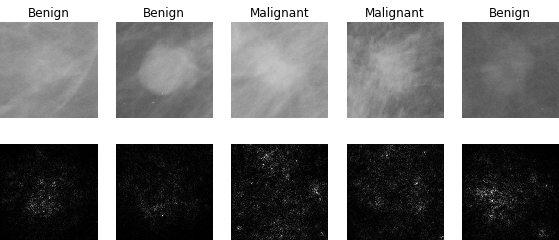

In our experiments, we use the Digital Database for Screening Mammography (DDSM) [4], a collaboratively maintained public dataset at the University of South Florida. It comprises approximately 2500 studies each containing both mediolateral oblique (MLO) and craniocaudal (CC) views of each breast. Each image is grayscale and accompanied by a mask specifying the region of the pre-segmented mass if present. Examples of benign and malignant masses are shown in Fig. 1.

5.3 Interpretability

Deep learning models often lack interpretability and as such are hard to adopt for practical use in medical settings. [21] describe a methodology to visualize saliency maps which show the regions of an image the network is sensitive to when making predictions. This is performed by computing the gradient of the image with respect to the unnormalized class scores. Regions with larger gradient indicate higher contribution to the prediction (brighter in Fig. 3). Both the AlexNet and GoogLeNet learn to attend to the edges of the mass, which is a high-signal criterion for diagnosis, while also paying attention to context.